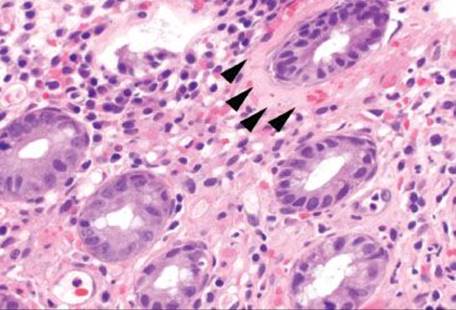

Figure 4.54 Ischemic colitis pattern, withered crypts. Crypt epithelium becomes damaged and sloughs, giving a “withered” appearance to the crypts (arrowheads). Compare these withered crypts to the right side of the photo, which are better preserved.